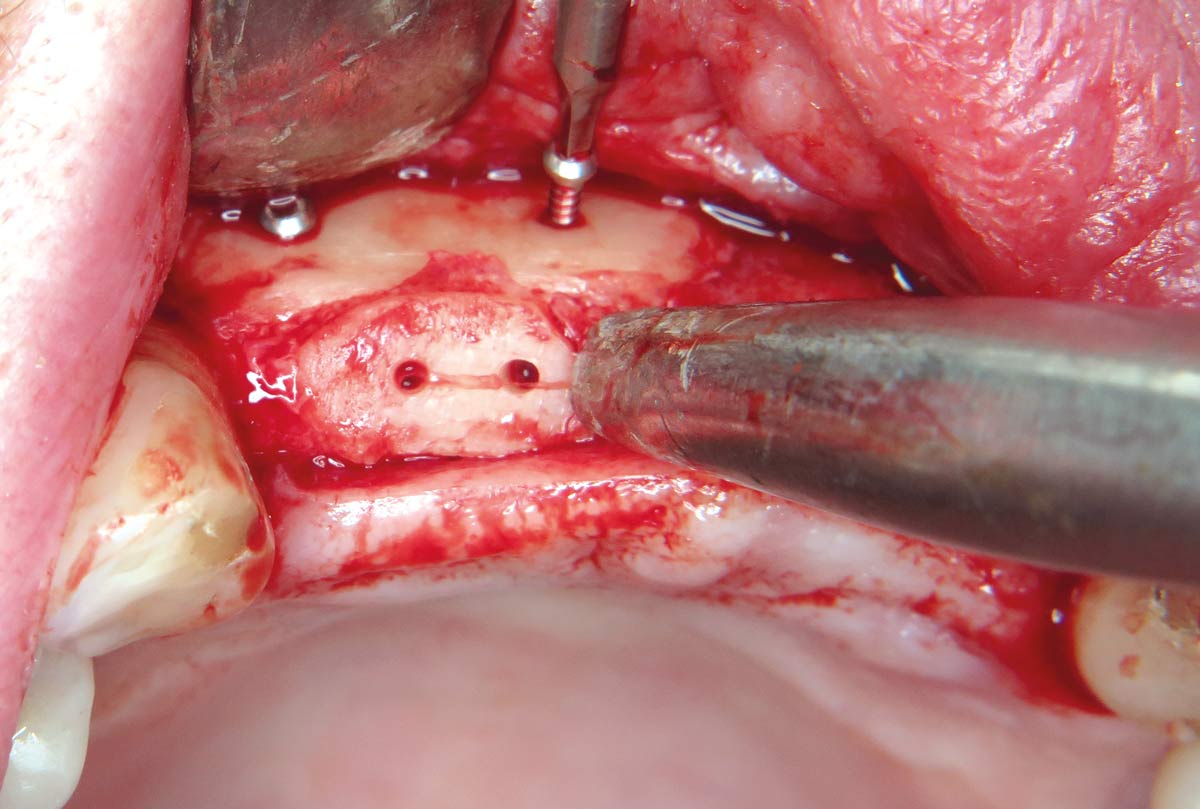

17 / 22 - Pilot drills for the four planned implants